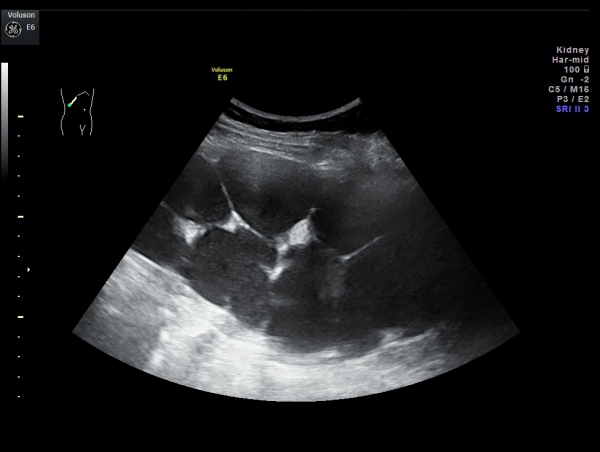

Вот гидронефротическая трансформация справа.

Спасибо за снимки, очень показательные. Лучше один раз увидеть, чем ... услышать.

Коллеги, давайте писать гидронефротическую трансформацию почки именно при такой картине (как на снимках), а не тогда, когда немного расширены лоханка и чашки.